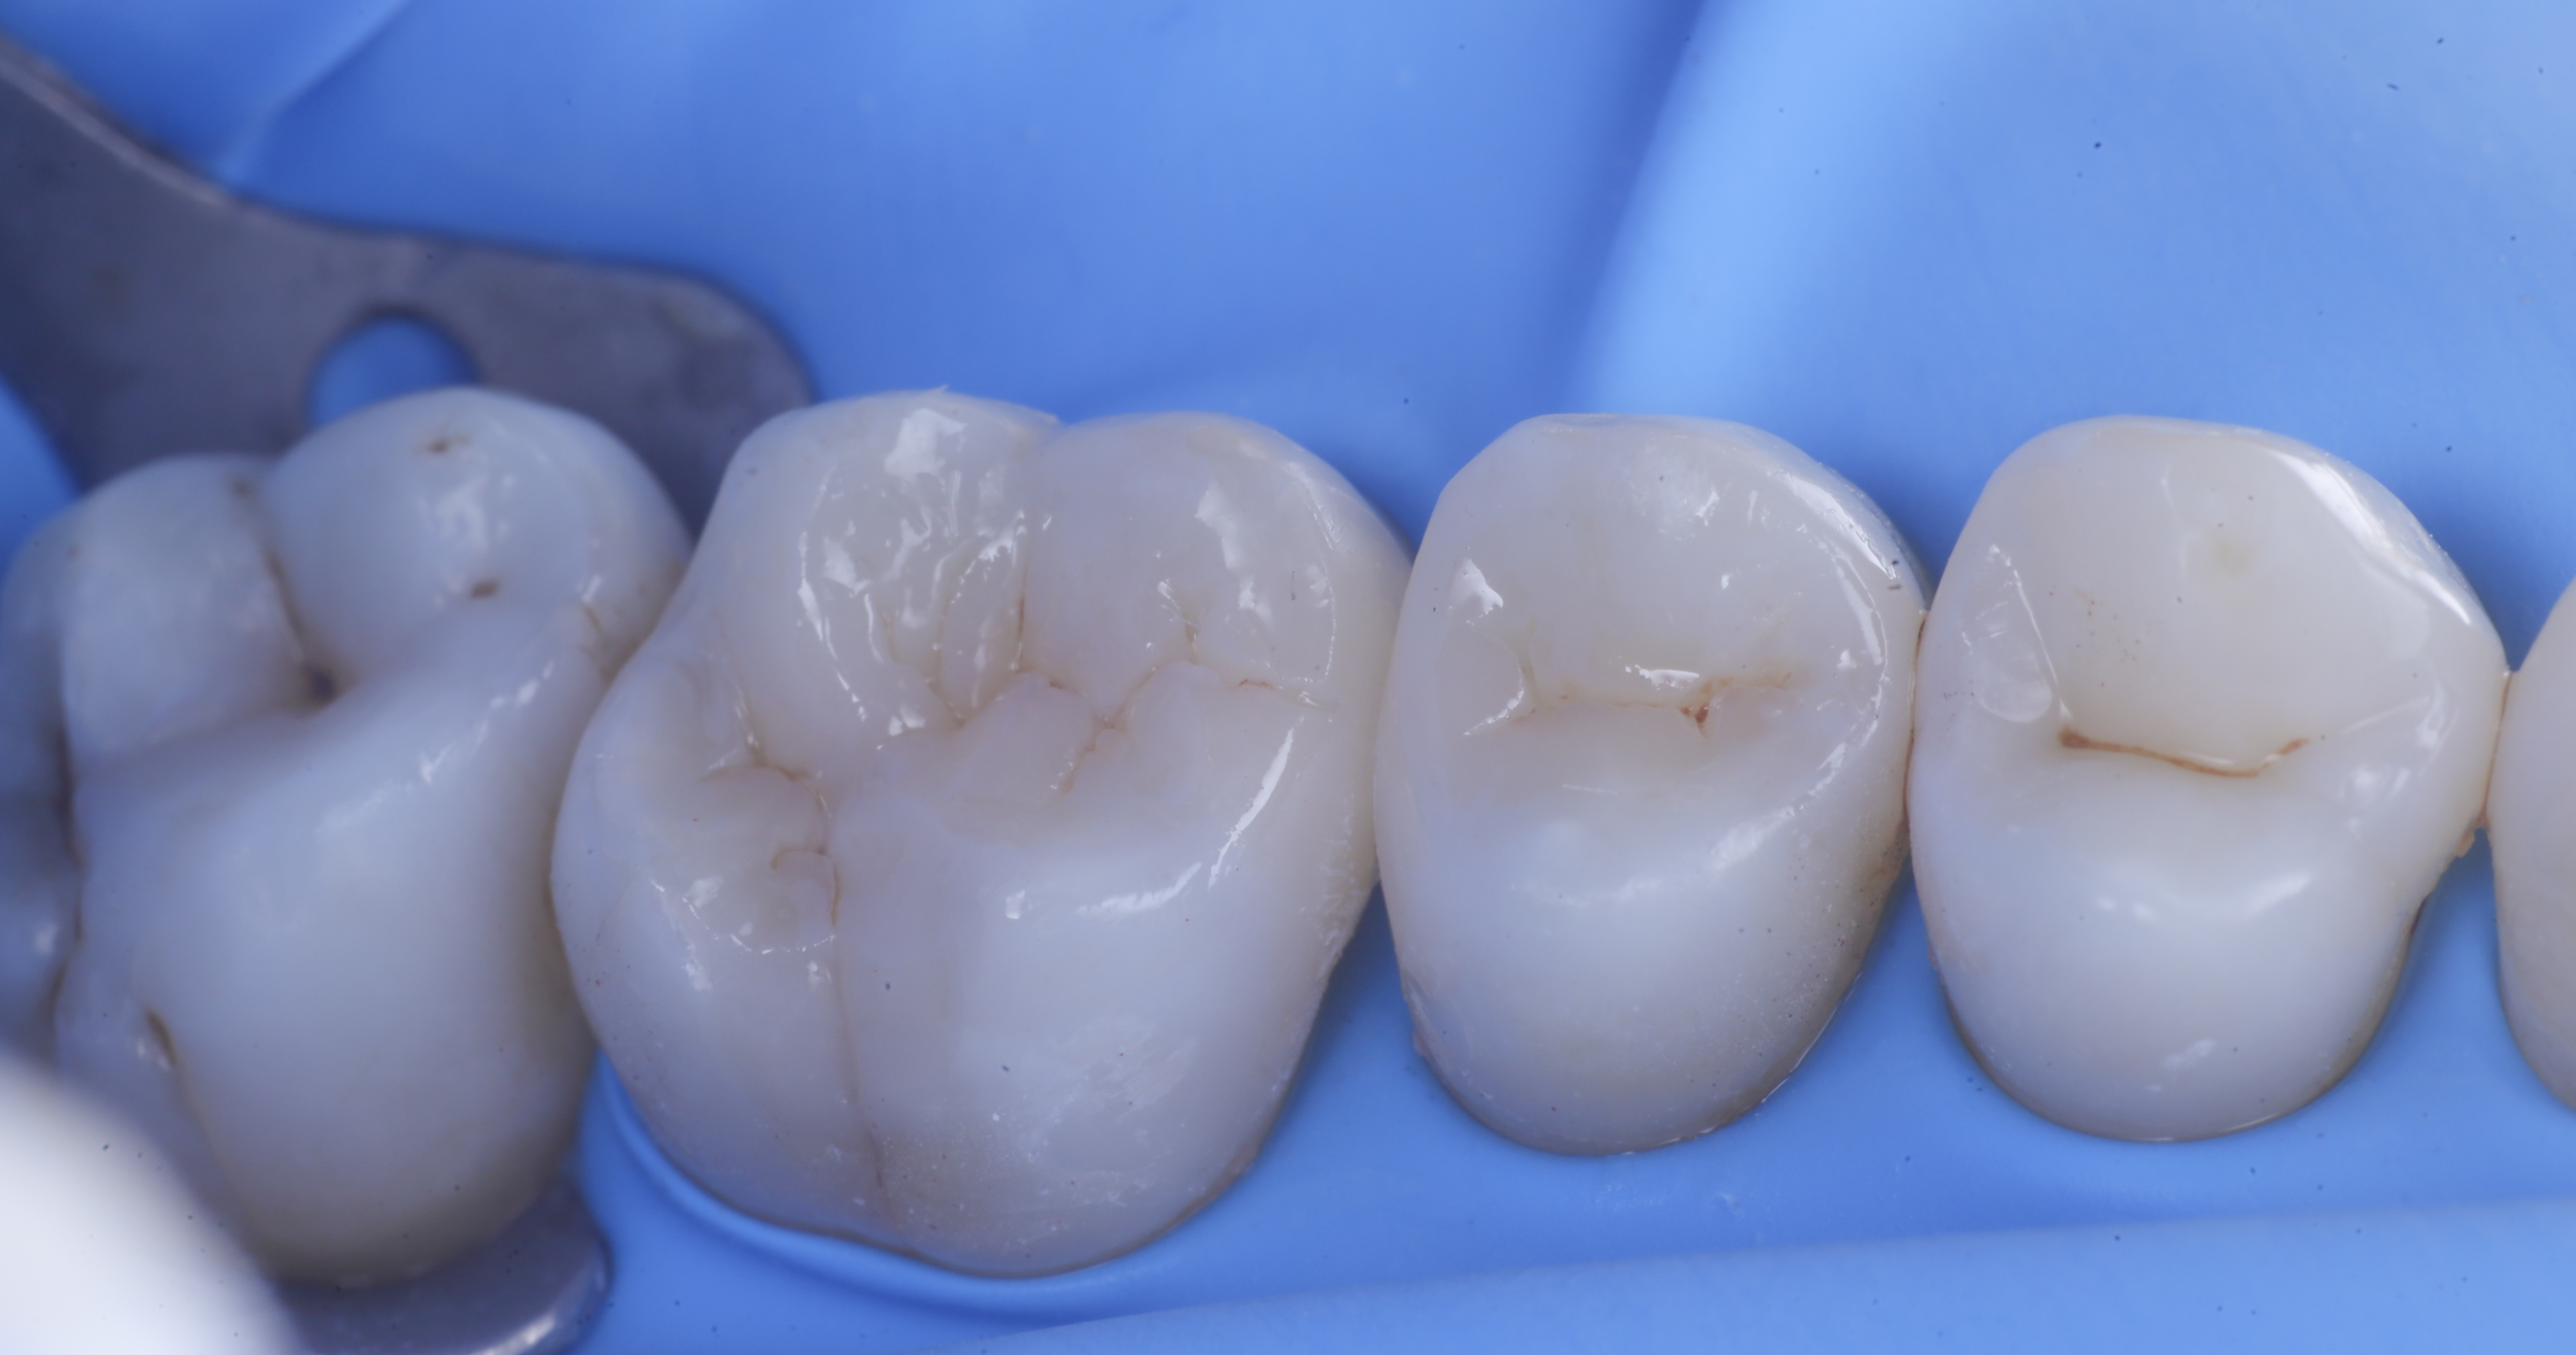

foto 2 Isolamento e aspetto delle cavità ultimate

foto 3 Aspetto vestibolare della cavità ultimate